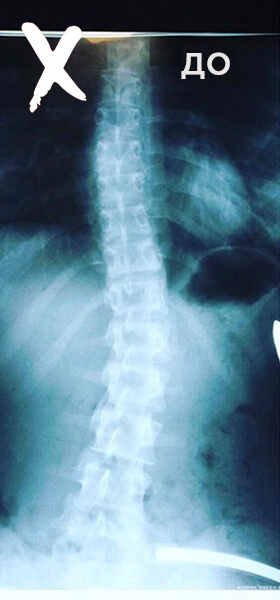

5 МЕСЯЦЕВ ЗАНЯТИЙ В DORSUM

ДЕВОЧКА, 16 ЛЕТ